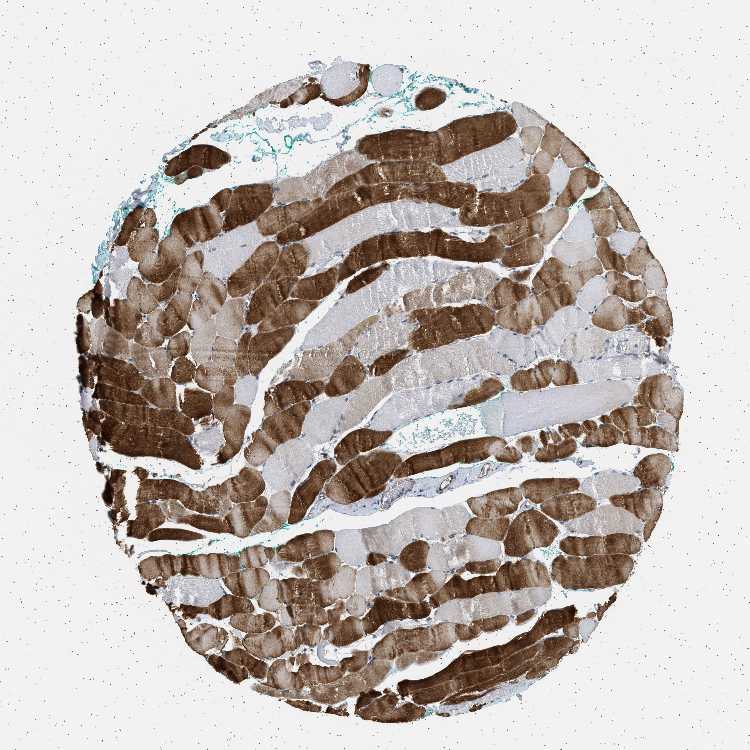

SKELETAL MUSCLE - Antibody stainingi

Antibody staining in the annotated cell types in the current human tissue is reported as not detected, low, medium, or high, based on conventional immunohistochemistry profiling in selected tissues. This score is based on the combination of the staining intensity and fraction of stained cells.

Each image is clickable and will lead to virtual microscopy that enables deeper exploration of all samples and also displays staining intensity scores, fraction scores and subcellular localization as well as patient and tissue information for each sample.

Antibody HPA018096

Myocytes High